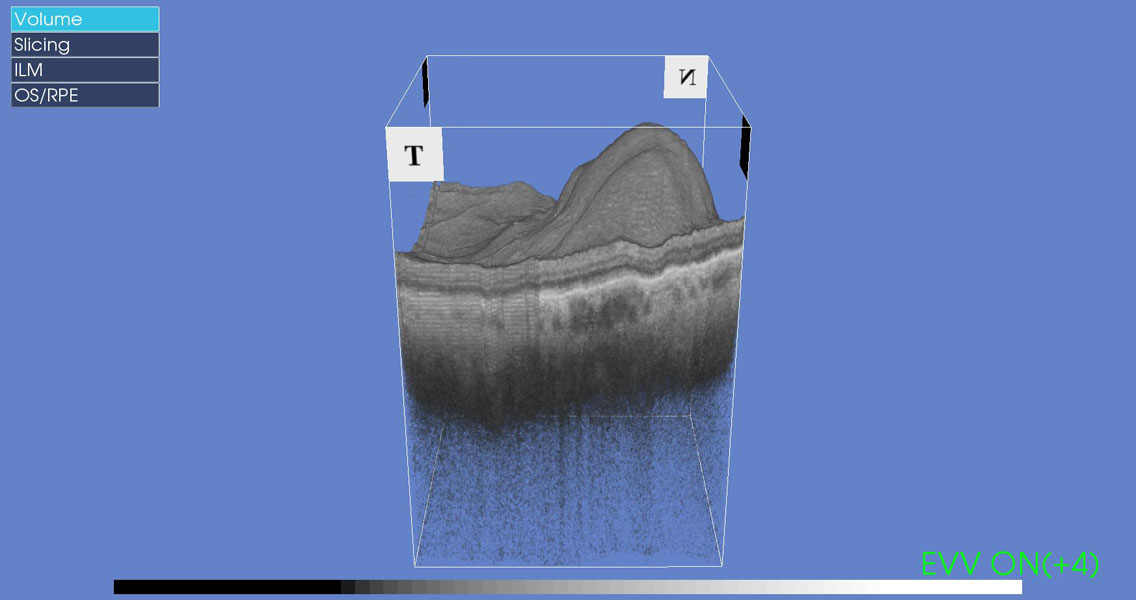

• Liquido o depósitos grasos en la retina y especialmente sobre la macula

• Desprendimiento de retina